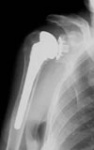

​Abnutzungserscheinungen des Schultergelenkes (Omarthrose) können ebenfalls endoprothetisch versorgt werden, wobei hier aufgrund der vorwiegend muskulär bedingten Gelenkführung einige Besonderheiten beachtet werden müssen, welche im Rahmen einer ambulanten Vorstellung abgeklärt werden.

Omarthrose Schultergelenksendoprothese